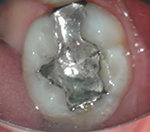

上のような小さな歯が、マイクロスコープではこのように見えています。

むし歯の治療(カリエス処置)

指の先ほどの歯の中の、むし歯の部分だけを除去しなければなりません。

むし歯の部分を取り損ねたら再発し、削り過ぎると歯を弱くしてしまうので、注意力と集中力が必要です。

マイクロスコープを用いれば視野を拡大して見られるため、健康な歯を痛めずむし歯の部分だけを除去できます。